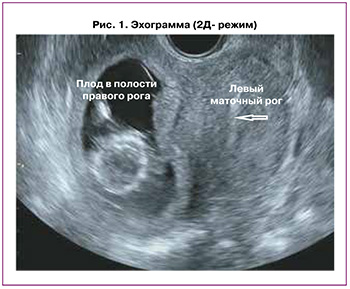

Данная беременность третья. Первая беременность (2012 г.) завершилась операцией кесарева сечения в сроке 37 недель в связи с отслойкой нормально расположенной плаценты. Вторая беременность (2016 г.) – самопроизвольный аборт в сроке 4 недели. Третья беременность (2018 г.) завершилась оперативным лечением внематочной беременности в сроке 3 недели в объеме: лапаротомия, тубэктомия слева. Четвертая беременность настоящая, не индуцированная. В 12 недель взята на учет по беременности в женскую консультацию. Проведено клинико-лабораторное обследование согласно действующему приказу № 1130н Министерства здравоохранения Российской Федерации от 20 октября 2020 г. на этапе женской консультации в полном объеме. Перинатальные скрининги проведены в регламентируемые сроки. По данным 1-го ультразвукового скрининга (в 12 недель 5 дней гестации): в полости правого маточного рога определялся 1 живой плод без пороков развития; полость левого рога умеренно расширена (до 16 мм), заполнена гипоэхогенным содержимым; толщина миометрия в области рубца (кесарево сечение) составляла до 4,0 мм; расположенная по задней стенке плацента достигала области внутреннего зева (эхограммы в двухмерном режиме и трехмерной реконструкции представлены на рисунках 1 и 2).